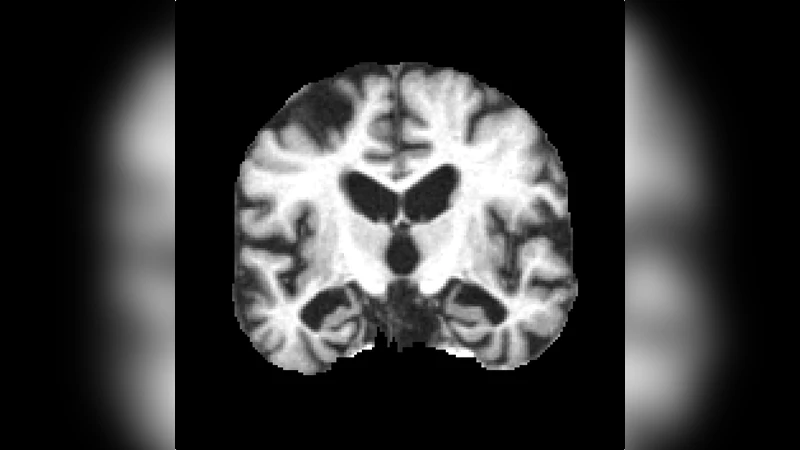

차원 축소의 핵심은 PCA를 이용한 ‘eigenbrain’ 추출이다. 저자는 전통적인 얼굴 인식에서 사용되는 eigenface 개념을 차용해, 전체 데이터셋의 특정 축(코로나와 축축)에서 평균 뇌 영상을 기준으로 주성분을 계산한다. 코라날 슬라이스와 축축 슬라이스 각각에서 여러 주성분을 도출했으며, 실험적으로 4번째와 7번째 주성분이 분류 성능을 가장 크게 향상시키는 것으로 확인돼 최종 피처에 포함되었다. 모든 피처는 평균을 0, 분산을 1로 정규화하여 SVM 학습 시 스케일 차이에 의한 편향을 최소화한다.